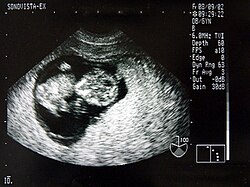

Das Ultraschallbild wird auch Sonogramm genannt.

Ein wesentlicher Vorteil der Sonografie gegenüber dem in der Medizin ebenfalls häufig verwendeten Röntgen liegt in der Unschädlichkeit der eingesetzten Schallwellen. Auch sensible Gewebe wie bei Ungeborenen werden nicht beschädigt, die Untersuchung verläuft schmerzfrei.

Neben der Herztonwehenschreibung (Kardiotokografie) ist sie ein Standardverfahren in der Schwangerschaftsvorsorge. Eine spezielle Untersuchung der Pränataldiagnostik zur Erkennung von Entwicklungsstörungen und körperlichen Besonderheiten ist der Feinultraschall.

Von den Monitorbildern werden zur Dokumentation Ausdrucke, sogenannte Sonogramme, oder gelegentlich Videoaufnahmen gemacht. Schwangeren wird häufig auch ein Bild ihres ungeborenen Kindes überlassen.